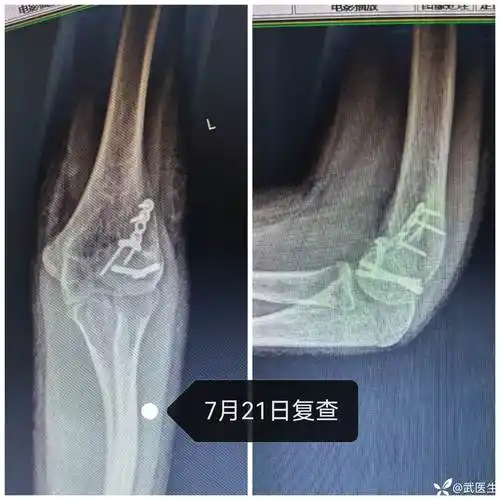

儿童肘关节骨折线诊断

儿童肘关节脱位外髁骨折1例

一例儿童肘关节骨折,如果第一次自己接诊,会漏诊么?